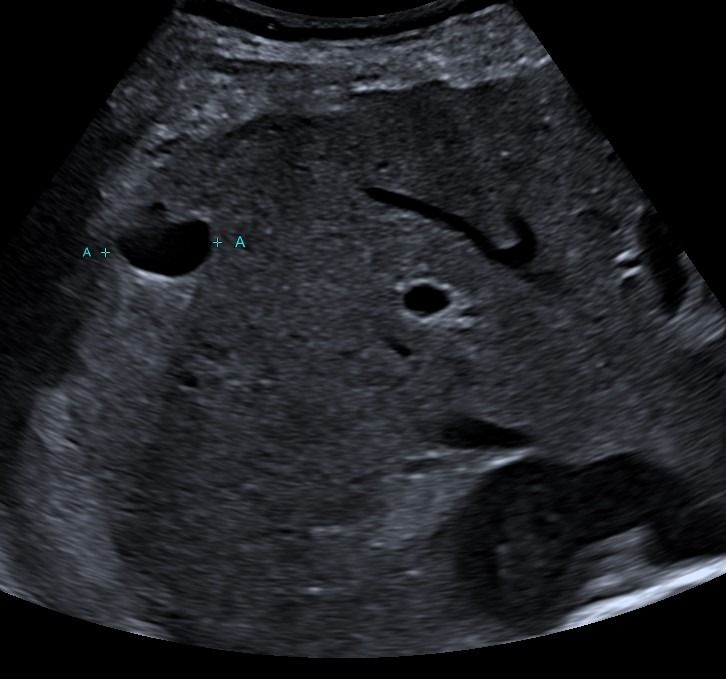

Τι μπορούμε να διαγνώσουμε με το Τriplex Κοιλιακής Αορτής;

Το Triplex Κοιλιακής Αορτής μπορεί να αξιολογήσει την παρουσία αθηρωμάτωσης ή στένωσης της κοιλιακής αορτής και να ανιχνεύσει πιθανό ανεύρυσμα.